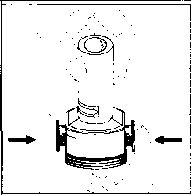

- Kenarlardaki iki kulakçığa (düğmelere) aynı anda ve sadece bir kez sıkıca basarak kapsülü deliniz.

5. Tozu kapsülden serbestlemek için:

Not: Kapsül bu aşamada parçalanabilir ve küçük jelatin parçacıkları ağzınıza ya da boğazınıza gelebilir. Fakat jelatin yenilebilir nitelikte olduğu için zararlı değildir._ 6. Nefesinizi dışarıya olabildiğince veriniz.